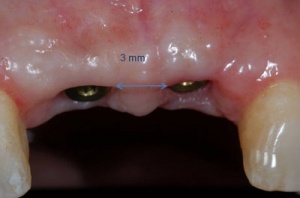

C'est la position spatiale de l'implant qui détermine la qualité de la prothèse en terme fonctionnel, esthétique.

Photos extraites du diaporama :